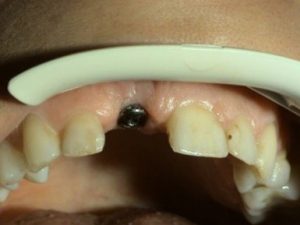

1. PHASE – implant insertion

2. PHASE – state before making immediate impressions